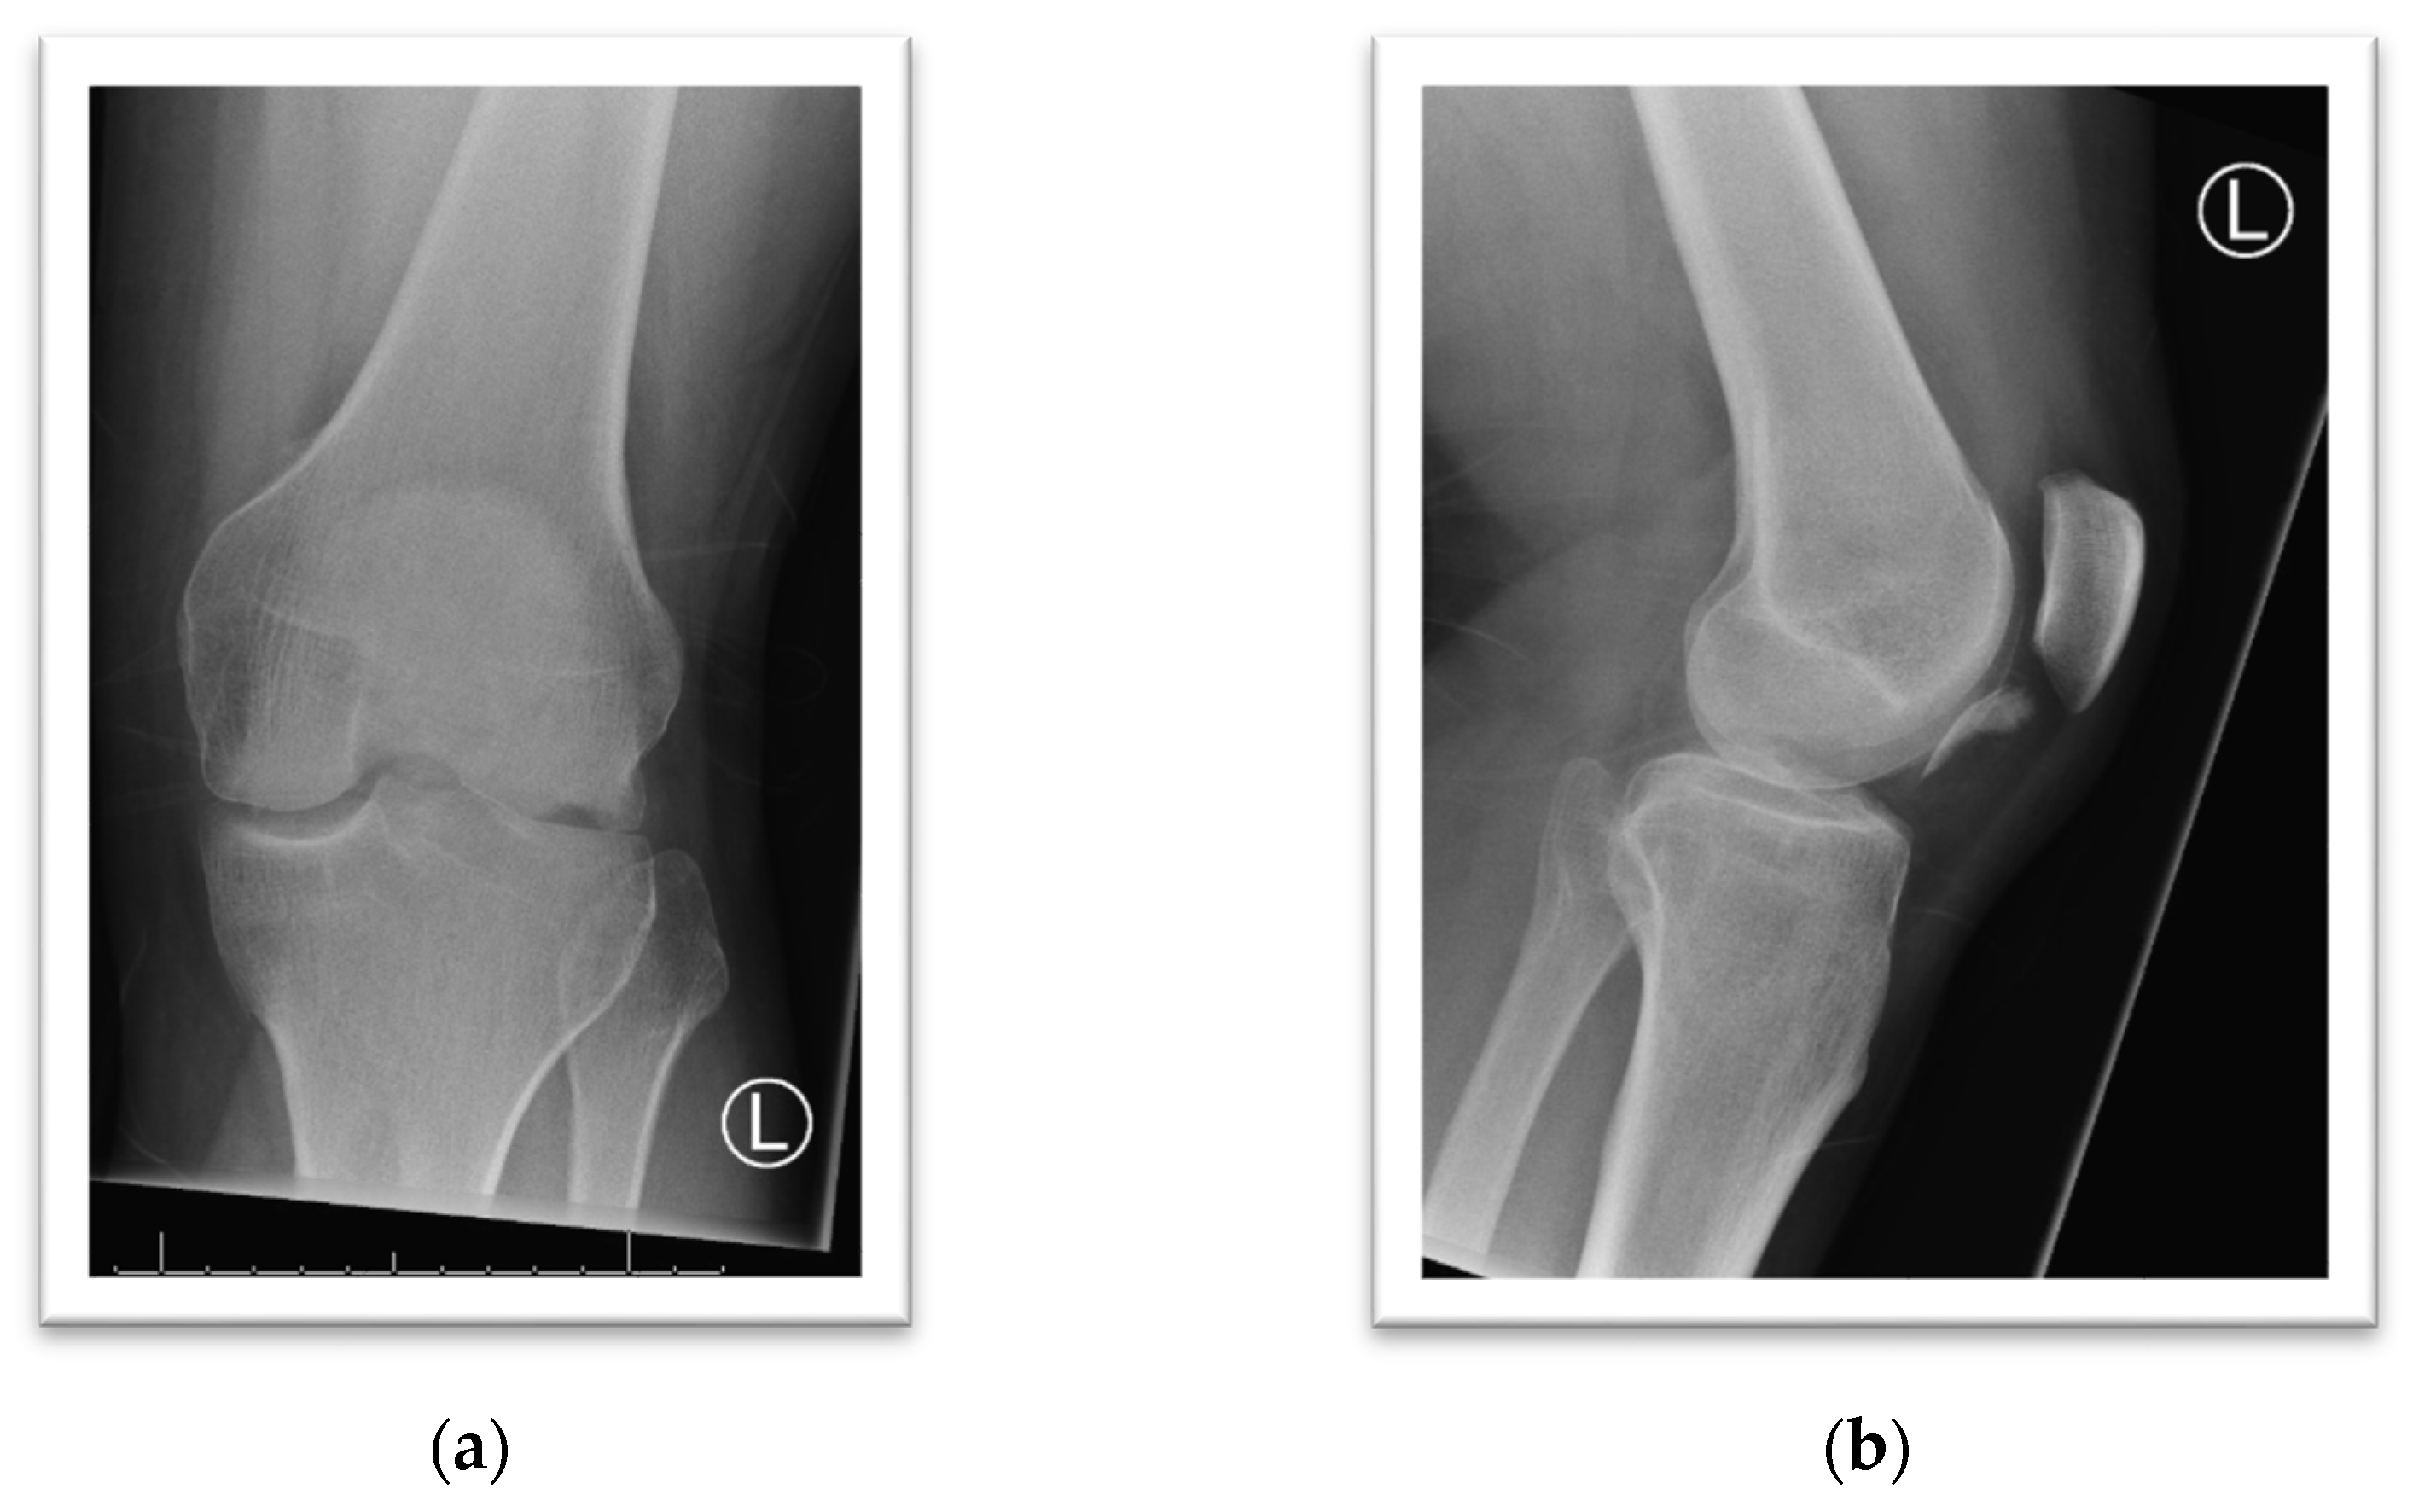

3. Case Presentation

4. Case Presentation

5. Case Presentation